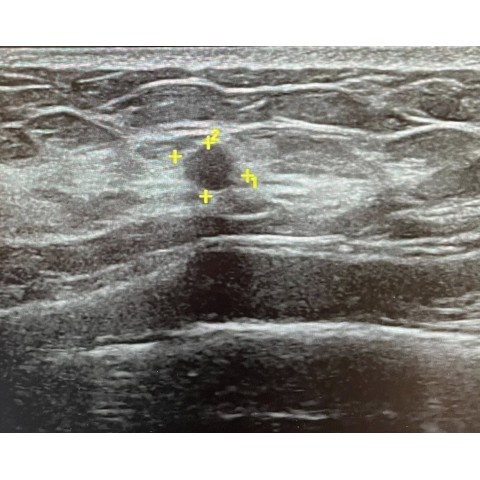

乳房超音波

乳房超音波 BIRADS

乳房硬塊切片檢查